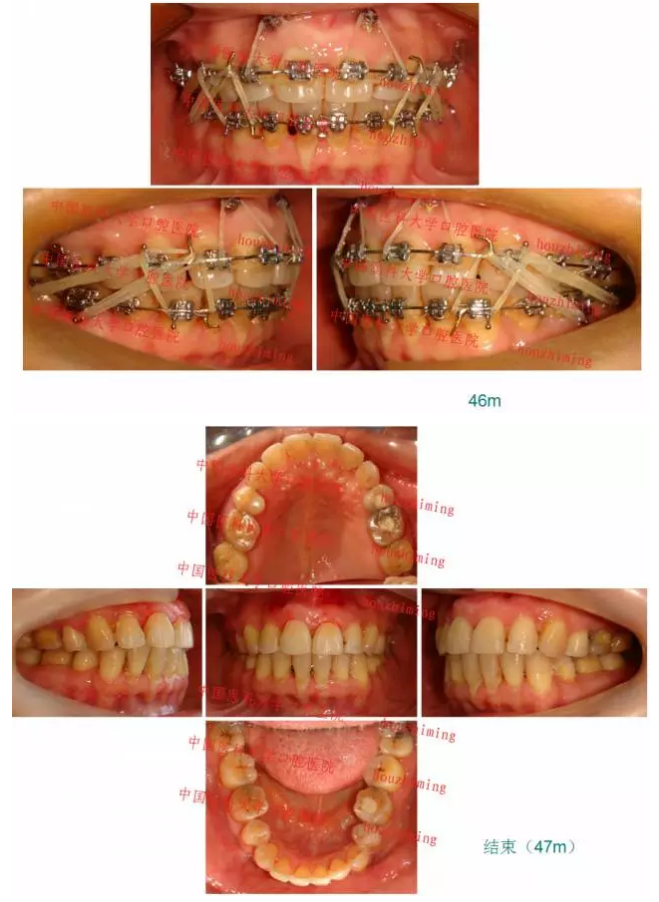

【原創(chuàng)博客】這樣的代償矯治大家滿意嗎?(重度骨性二類)——侯志明

QQ圖片20150824150825.png

QQ圖片20150824150547.png

QQ圖片20150824150559.png

QQ圖片20150824150613.png

QQ圖片20150824150628.png

QQ圖片20150824150643.png

QQ圖片20150824150701.png

QQ圖片20150824150716.png

QQ圖片20150824150729.png

QQ圖片20150824150743.png

QQ圖片20150824150805.png